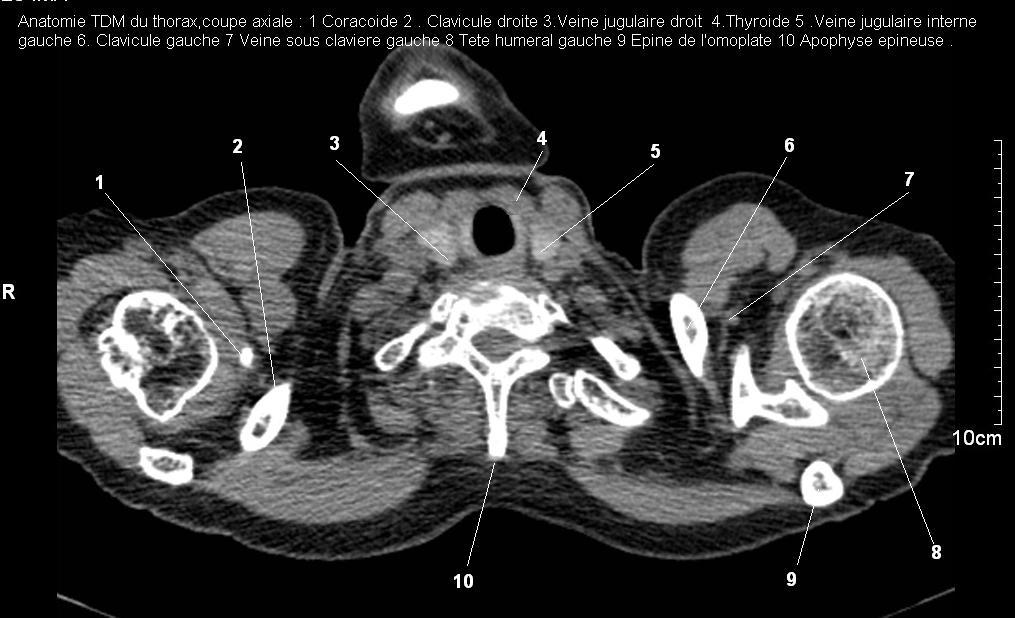

Radioanatomie pulmonaire ( image radiologie

thoracique normale )- La Tomodensitometrie du thorax (

coupes axiales fenetre mediastinale ) |

La fenetre mediastinale permettre

d'etudier anatomie du mediastin et les structures vasculaires

en coupes axiales de 0,5-1cm sur le thorax . Ceux qui

s'installent travers le thorax de C4 a L1, L2

a n'a pas de contrast et se donnent des resutats

suivantes : |